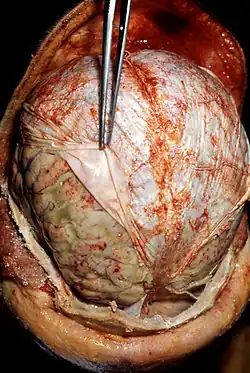

Post mortem

Eine Meningitis kann auch noch nach dem Tode festgestellt werden. Dabei finden sich insbesondere an Pia mater und Arachnoidea ausgedehnte entzündliche Veränderungen. Dadurch, dass neutrophile Granulozyten in den Liquor und die Gehirnbasis (schädelbasisnaher Anteil des Gehirns) zu Lebzeiten eingewandert sind, kann sich an den Hirnnerven, dem Rückenmark oder den Hirnarterien Eiter finden.[63]